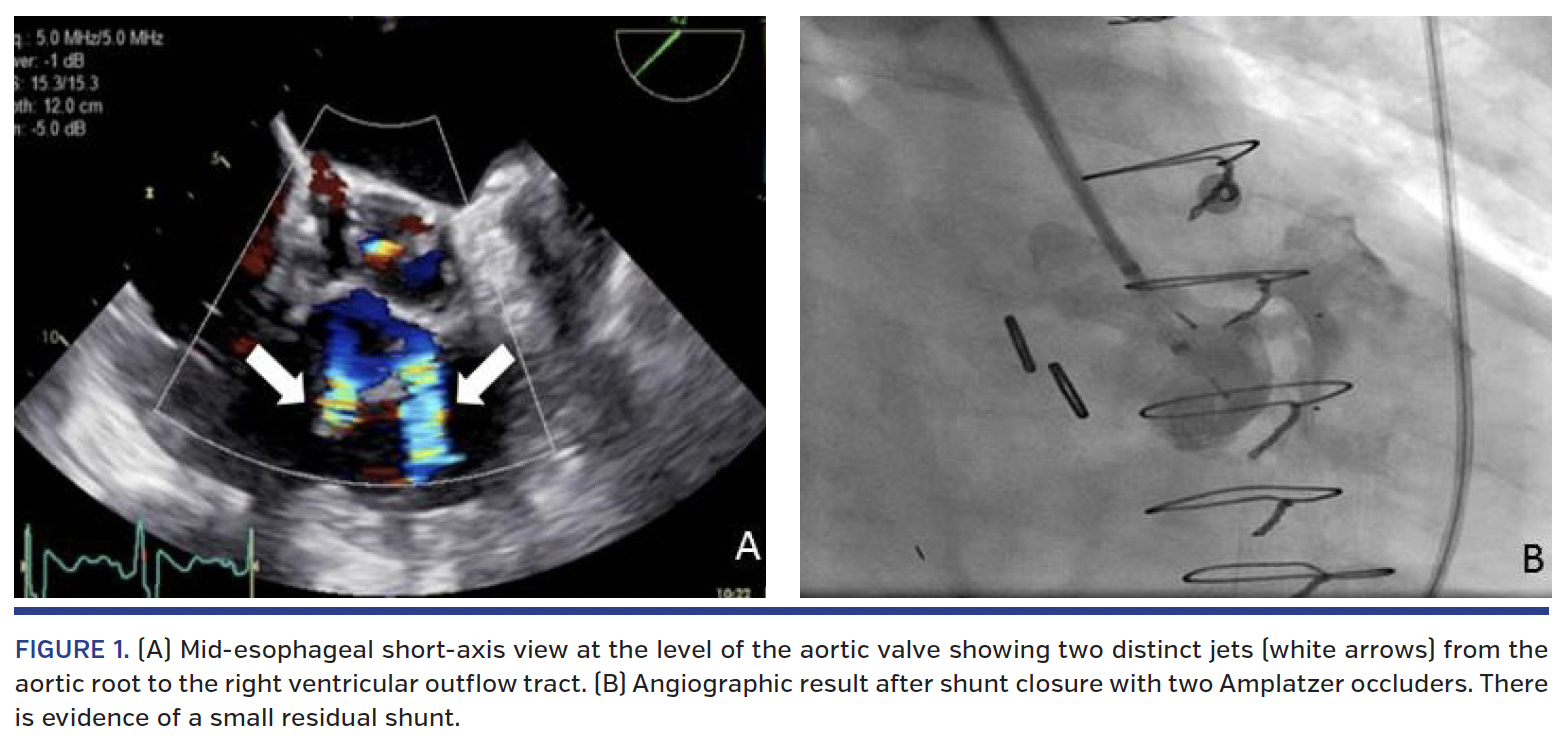

An 86-year-old man presented with shortness of breath two months after surgical resection of a right ventricular outflow tract (RVOT) mass. Physical examination revealed jugular venous distention and a continuous murmur over the second left sternal border. An echocardiogram performed revealed an abnormal color Doppler signal within the RVOT. Transesophageal echocardiogram demonstrated two communications between the aortic root and the RVOT (Figure 1A; Videos 1 and 2). The shunts were felt to be iatrogenic from his recent cardiac surgery. He was deemed a poor surgical candidate and percutaneous closure of both fistulae under monitored anesthesia care with transthoracic echocardiogram and fluoroscopy guidance was elected. Initial left ventriculogram demonstrated the shunts (Video 3). The first defect measured 5 mm in diameter, and the second measured 7 mm. A 6 x 4 mm and a 6 x 6 mm Amplatzer duct occluder II (AGA Medical Corporation) were used to close the defects (Figure 1B; Videos 4 and 5). The patient improved significantly and has done well at 6-month follow-up.